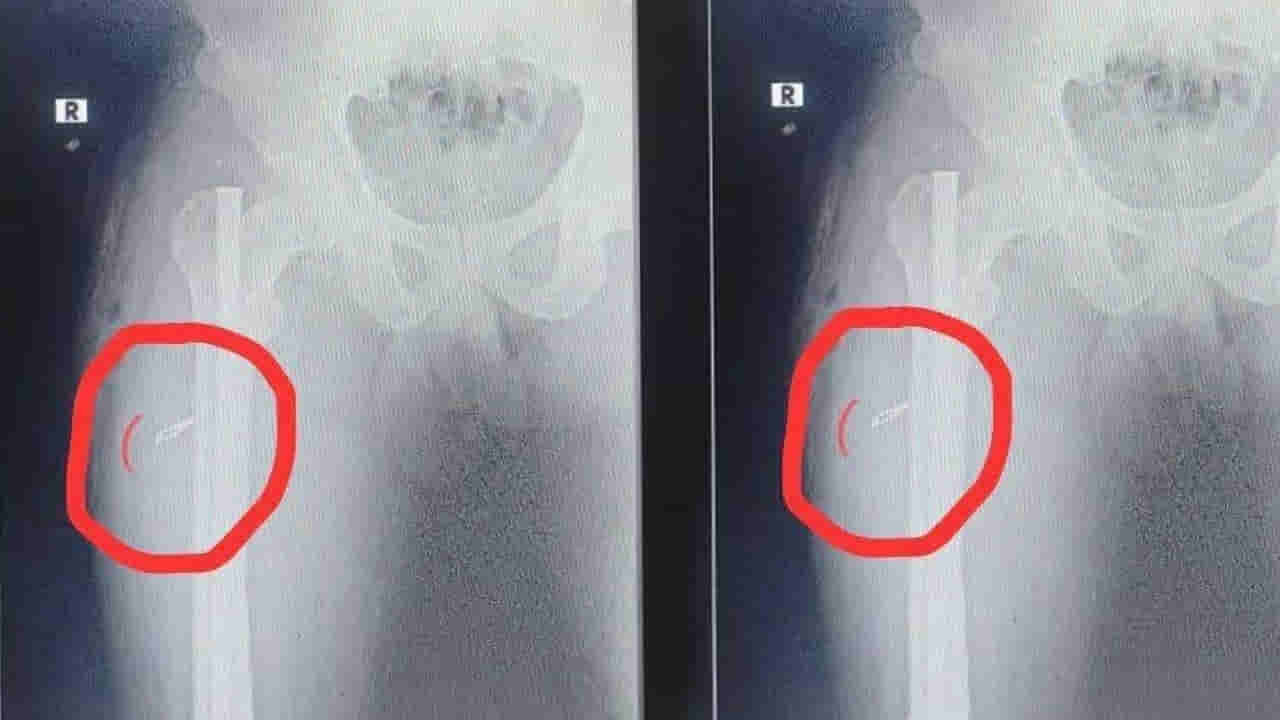

కాకినాడ జిల్లా తుని మండలం ఎస్.అన్నవరం పంచాయితీ రామకృష్ణ నగరంకు చెందిన చిన్న(25) అనే వ్యక్తి ఏడాదిన్నర క్రితం కాలుకు గాయం తగలడంతో వైజాగ్లో గాయంకు ఆపరేషన్ చేయించుకున్నాడు. అప్పట్లో కాలికి బలంగా దెబ్బతగలడంతో లోపలి భాగంలో రాడ్ అమర్చి ఆపరేషన్ చేశారు. ఏడాదిన్నర గడిచిన తర్వాత వెలుపల ఉన్న ఒక బోల్ట్ తీస్తే త్వరగా సెట్ అవుతుందని చెప్పడంతో.. కాలులో రాడ్కు ఉన్న బోల్ట్ తీయించుకునేందుకు తుని గవర్నమెంట్ హాస్పిటల్కి వెళ్లాడు. అక్కడ సిబ్బంది ఆపరేషన్ చేసి రాడ్ బోల్ట్ వెలపలకు తీశారు. కానీ కాలులో మాత్రం సిజెరియన్ బ్లేడు ఒక్కటి ఉంచి యధావిధిగా కుట్లు వేయడంతో.. ఆ విషయాన్ని స్కానింగ్లో గుర్తించాడు సదరు బాధితుడు.

హాస్పిటల్ సిబ్బంది ఎంతటి బాధ్యరాహిత్యంగా ఉంటున్నారో ఇలాంటి సంఘటనలు చూస్తుంటే అర్ధం అవుతుందంటూ బాధితుడు ఆవేదన వ్యక్తం చేశాడు. ఇలా చేశారేంటని ఆస్పత్రి వైద్యులను ప్రశ్నిస్తే పేషెంట్ మీద తిరగబడ్డారు ఆ సిబ్బంది. చివరకు మళ్ళీ ఆపరేషన్ చేసి బ్లేడ్ తీసి హాస్పటల్లో వైద్యులు చికిత్స అందిస్తున్నారు. ఇది ప్రస్తుతం ప్రభుత్వ హాస్పటల్లో పనితీరు అంటూ స్థానికులు